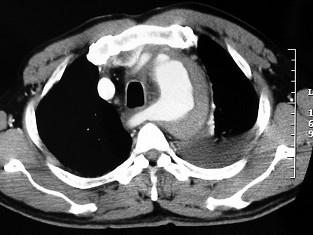

问题 男,58岁,有高血压病史,突发胸背剧痛,CT扫描如图,其最可能的诊断为 ( )

选项 A.主动脉瘤 B.主动脉假性动脉瘤 C.主动脉窦瘤破裂 D.高安氏病 E.主动脉夹层动脉瘤

答案 E